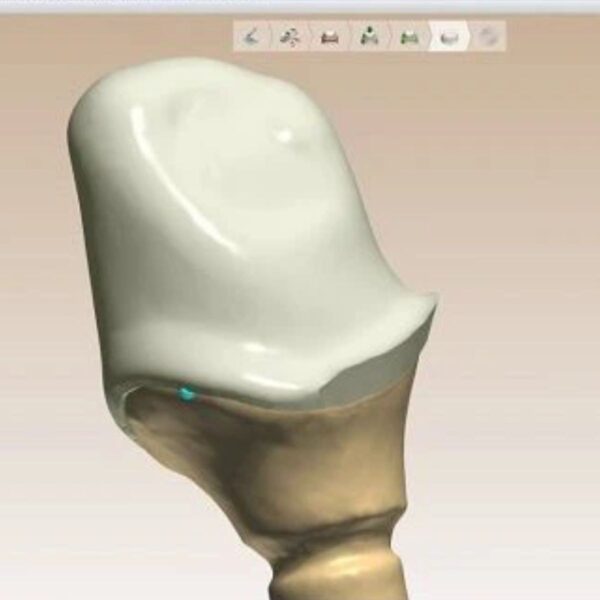

Conservative designs with perfect internal adaptation.

- Engineering: Drill Radius Compensation to prevent binding.